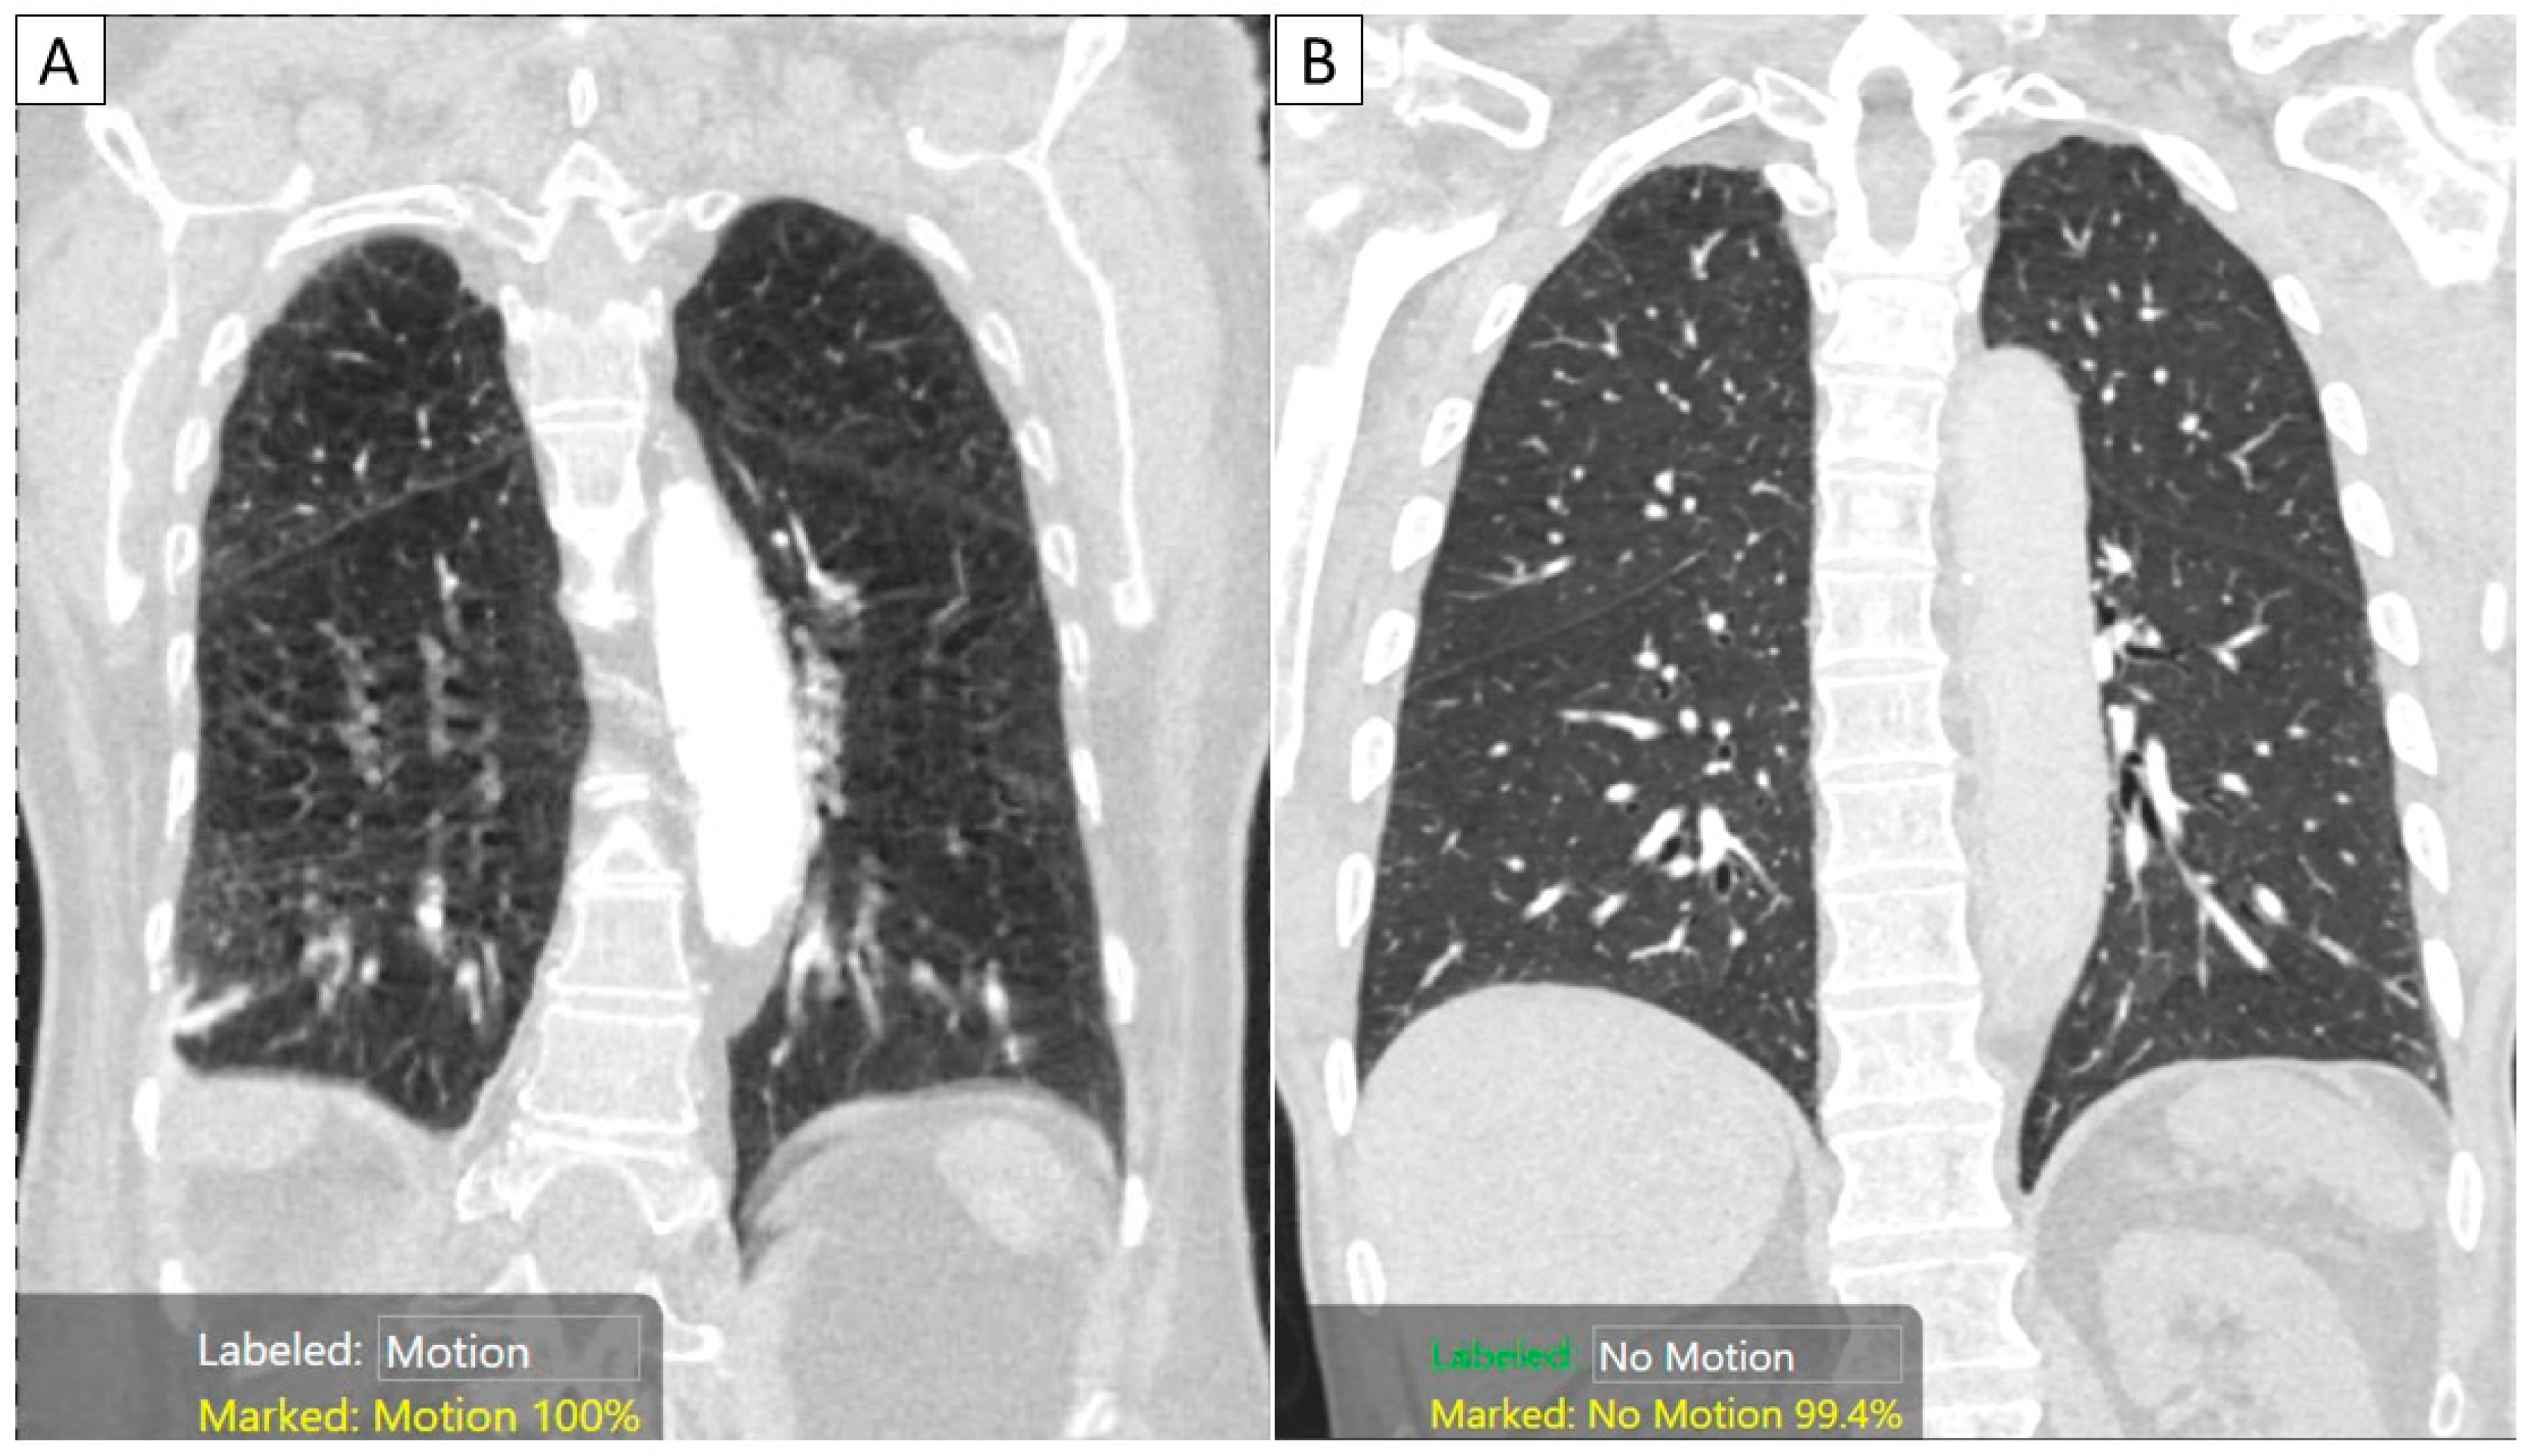

Comparison of Motion Artifacts on CT Images Obtained in the Ultrafast Motion Artifact Results — we present a unique dataset of structural brain mri images collected from 148 healthy adults which includes both. — in this review, we first examine the physical origins of motion artifacts and then summarize the main. in this report we examine impact of motion on signal intensity and rsfc correlations. Pi = parallel imaging, rf =. Motion Artifact Results.

Diagnostics Free FullText AutoDetection of Motion Artifacts on CT Motion Artifact Results Overview of commonly occurring artifacts at routine mri. — in this review, we first examine the physical origins of motion artifacts and then summarize the main. Minimizing artifact by changing imaging parameters. — we present a unique dataset of structural brain mri images collected from 148 healthy adults which includes both. — figure 1. in this. Motion Artifact Results.